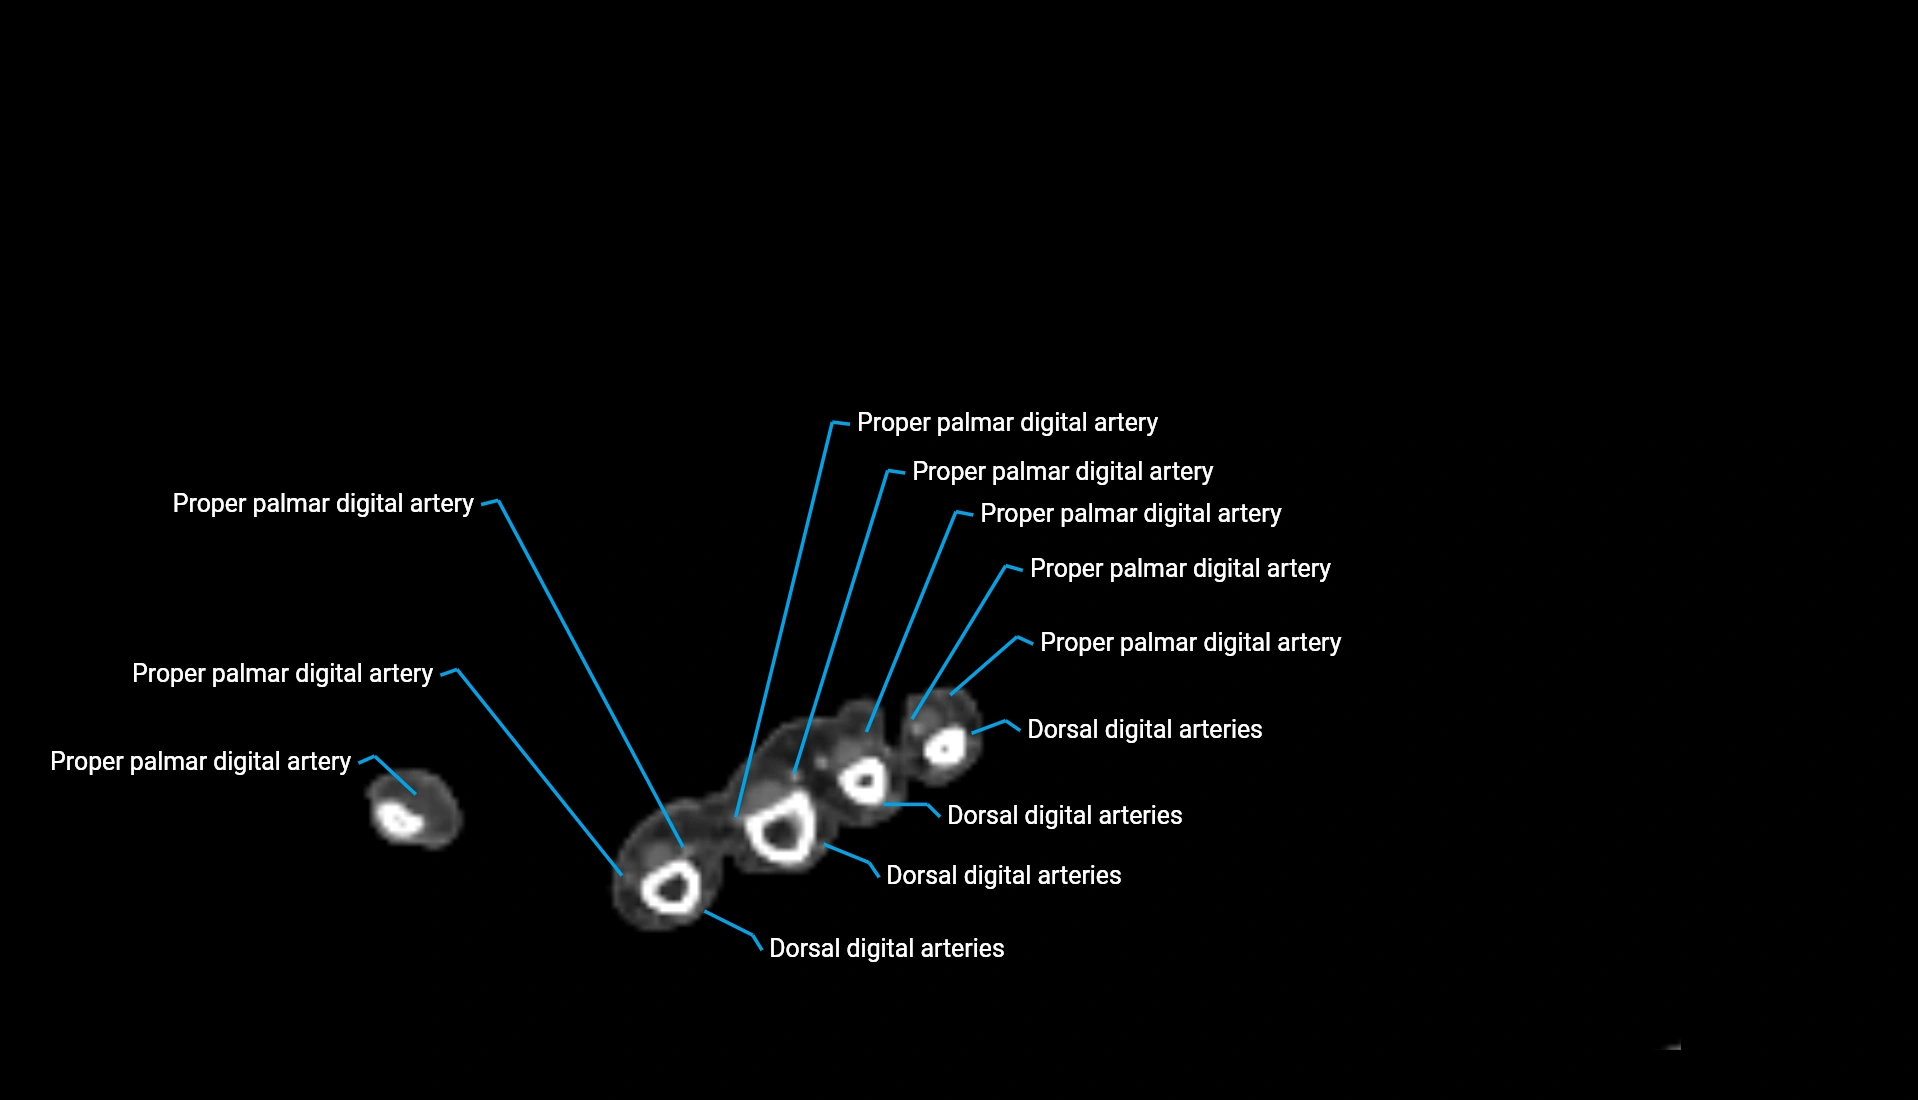

CT Appearance

Non-Contrast CT:

• Cortex: High-density, sharply defined

• Subchondral bone: Dense cancellous matrix

• Articular surface: Smooth concave contour articulating with the capitellum

• Excellent for evaluating bone integrity, alignment, and subtle fractures